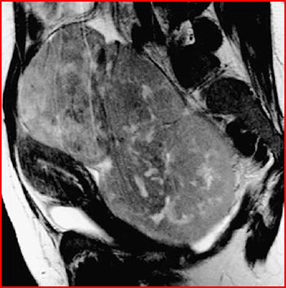

MRI shows a mass-free uterus, with no evidence of normal ovaries. The masses are approximately 13 cm in diameter and have low signal intensity on T1-weighted images and increased avidity after gadolin administration. On T2-weighted images the mass is hyperintense and the peripheral lesions probably correspond to ovarian follicles (Figures 4-6).

Figure 4: Axial T1-weighted MRI image, showing low signal intensity of the mass

Figure 5: Coronal T1-weighted MRI image, performed by administration of intravenous gadolin, shows low signal intensity of the mass, the black arrow highlights an increase in the septal area. The second mass, white arrow, extends into the upper left quadrant.

Figure 6: Sagittal T2-weighted MRI image of the pelvis, shows that the ovarian mass posterior to the uterus has an heterogeneous, intermediate-high signal intensity, the follicles in the periphery (arrow points), have a high signal intensity. The asterisk highlights the free liquid in the Douglas cord.

The aim of obtaining a certain diagnosis through the use of imaging techniques, integrated with biopsy and immunohistochemical examination is to avoid unnecessary and extensive surgery in very young patients. Another author who described the figures that appear on imaging in the case of lymphoma with ovarian localization is Mitsumori [6] in fact reports the case of a 12-year-old girl suffering from primary ovarian lymphoma, accurately describing the images provided by the MRI (Figures 11-13).

The T2-weighted image highlights a solid mass with an intermediate signal intensity and a hyperintensity of the septal structures. When gadopentetate dimeglumine is administered intravenously, T1-weighted images reveal marked enlargement of the septa.Numerous small, regular-walled cysts are visible at the periphery of the tumor. In the contralateral ovary, three nonconnected nodules are evident on a T2-weighted image.

These nodules show the same signal intensity as the tumor mass. A needle aspiration biopsy reveals the presence of B-cell non-Hodgking lymphoma. There are three characteristic images in this case:

1) septal structures are hyperintense on T2-weighted images.

2) the periphery of the tumor is delimited by regularly arranged cysts of small size, of uniform volume and with smooth walls (presumably these are ovarian follicles).

3) three independent nodules are present in the contralateral ovary.

Figure 11: Sagittal T2-weighted MRI image shows that the tumor has intermediate signal intensity (open arrows) and there are hyperintense septal structures within the tumor (arrowheads). In the contralateral ovary there are three disconnected nodules (black arrows).

Figure 12: Sagittal T1-weighted MRI image, septa show increased signal intensity after administration of gadopentetate dimeglumine (arrowheads).

Figure 13: Axial T1-weighted MRI images with gadopentetate dimeglumine administration show many small, uniformly sized, smooth-walled cysts at the periphery of the mass (arrowheads).